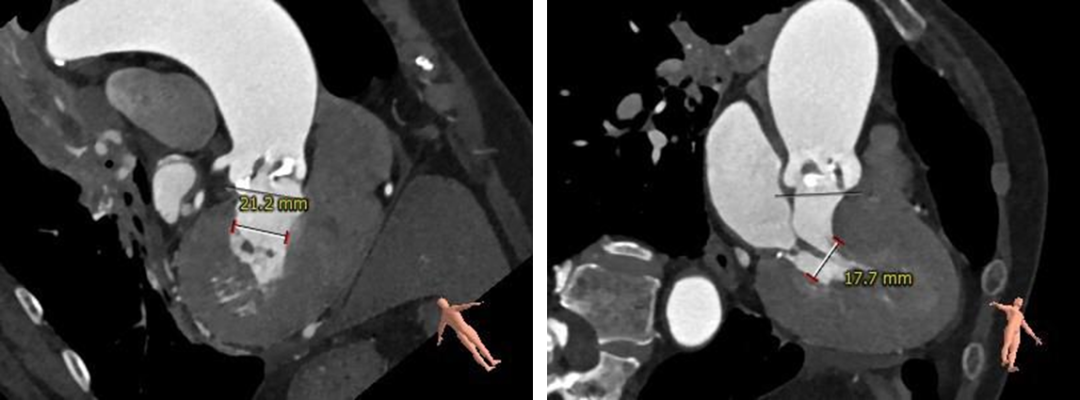

● 心室肌肥厚,收缩期左室内径偏小(17.7*21.1mm),存在术中循环崩溃风险。

左室心肌肥厚,收缩期内径显著偏小(17.7*21.2mm)。